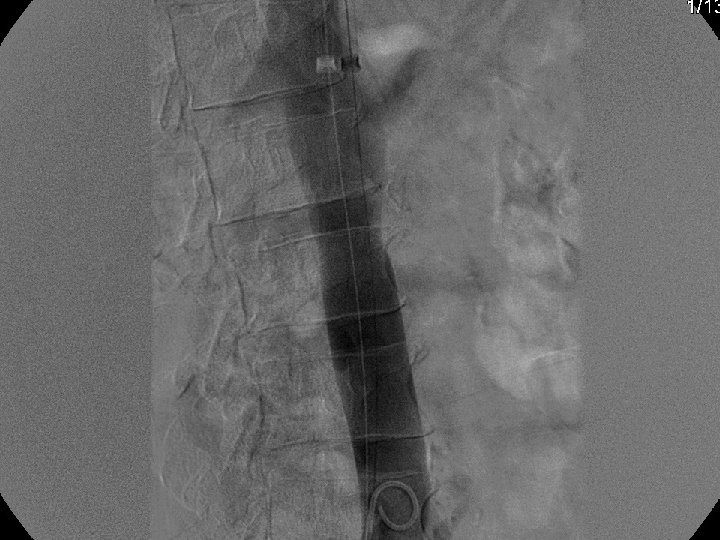

IVC Filter Removal Straight forward and Complex

Removal of an “Intravascular Foreign Body” Straight forward Loop snare Grasping device Complex Multiple devices used including angioplasty balloons, bronchoscopy forceps, and the“in situ” snare technique.

Retrieval with a snare and a long sheath or guiding catheter Günther Tulip (Cook) Celect (Cook) Opt Ease (Cordis Endovascular) Option (Angiotech) G 2 X, Eclipse, Meridian (Bard)

Recovery (G 2) Retrieval

Can a Permanent IVC Filter be Removed?